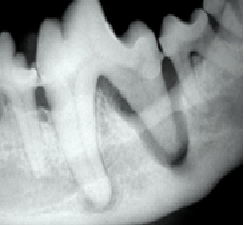

Because it is the best and safest way to care for your pet’s oral health. A dental cleaning is an unsettling experience even for a human. For your pet, it would be terrifying, and dangerous. In order to provide your pet with the best quality dental care, we must be able to look into the entire mouth, x-ray all the teeth to look for fractures and abscesses, probe the gums, scale the tartar and bacteria off of the visible tooth surfaces as well as under the gumline, and then polish all the teeth. Your pet would never allow us to do this while they are awake.

Often, when we have x-rayed the mouth and cleaned off the tartar, we find problems: fractures, loose teeth, and abscesses. Very often, these situations require that the affected teeth be extracted. If possible, we will try to do the extractions on the day of the dental cleaning. However, it is usually better for your animal to have these done as a separate procedure on another day. Either way, we will explain the situation to you and give you an estimate of costs so that you can be prepared.